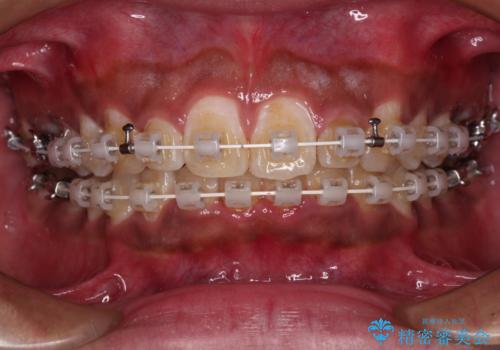

- 審美装置

抜歯は行わず、補助装置を用いて上顎歯列全体を後方移動させ、ワイヤー装置にて奥歯の咬み合わせを改善していくこととしました。